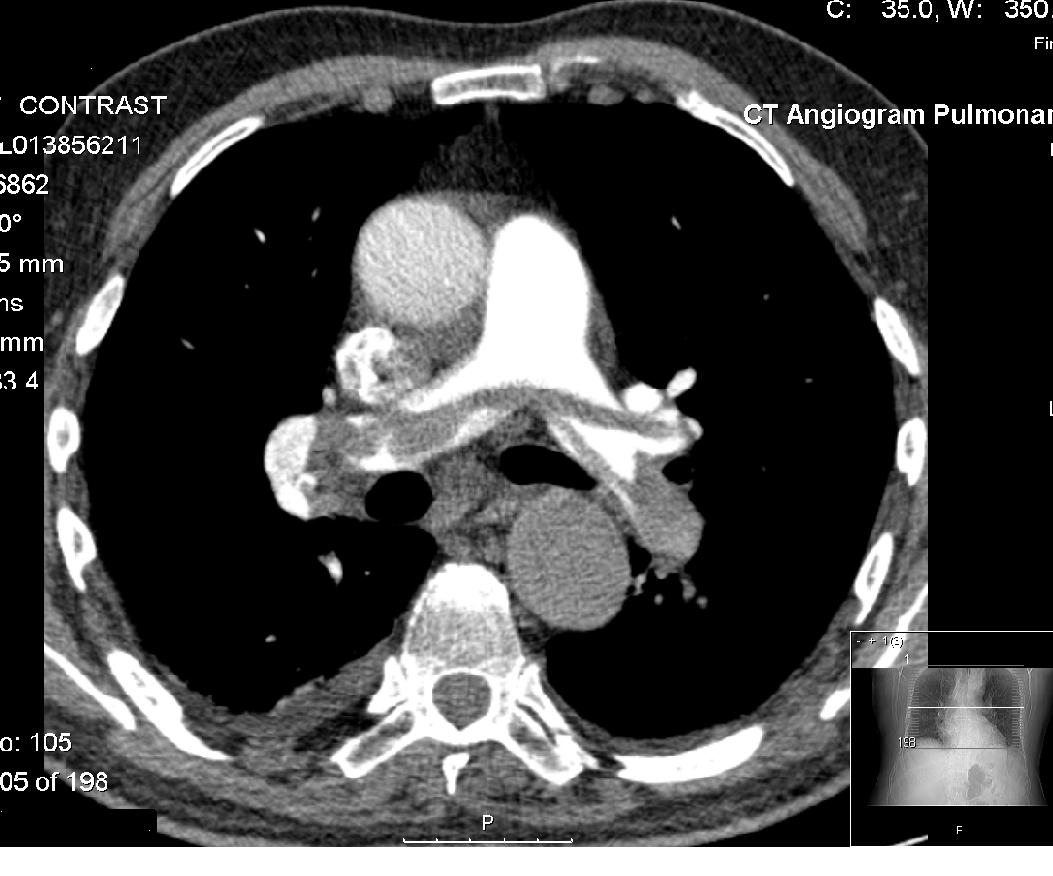

سی تی اسکن: سی تی اسکن ریه یک روش دقیق و سریع در ارزیابی آمبولی ریه است و امروزه جایگزین اسکن هسته ای و بقیه تستها شده است.

آنژیوگرام ریوی: در این روش با استفاده از لوله های باریکی به نام کاتتر ، ماده حاجب مستقیما به داخل شریان ریوی تزریق شده و با استفاده از دستگاه آنژیوگرافی تصاویر عروق ریه و لخته های داخل آن بررسی می شود. از این روش قبلا زیاد استفاده می شد ولی امروزه با وجود سی تی اسکن استفاده از آن محدودتر شده است.